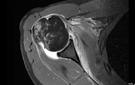

Weitere zusätzliche Informationen, insbesondere über den Zustand des Weichteilgewebes, kann eine sonographische Untersuchung (Ultraschall) erbringen, in bestimmten Fällen kann eine kernspintomographische Untersuchung (MRT) hilfreich sein.

Um das gesamte Ausmaß der Verletzung zu bestimmen wird zumeist eine kernspintomographische Untersuchung erfolgen.